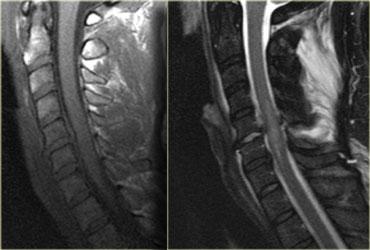

Bong gân tăng gấp (3)

MRI giải thích tình trạng thần kinh của bệnh nhân này.

Các dấu hiệu trên MRI bao gồm:

- Tổn thương mô mềm nặng nề ở các cấu trúc cạnh sống phía sau, đặc biệt tại mức C5-6, nơi dây chằng gian gai và dây chằng vàng bị đứt

- Rách đĩa đệm C5-6 với di lệch ra phía sau C5

- Phù nề tủy sống lan rộng

Tiếp tục với hình ảnh mặt cắt axial.

Hình ảnh axial cho thấy tổn thương tủy sống và ngoài ra còn có sự vắng mặt của khoảng trống dòng chảy (flow void) ở động mạch đốt sống phải.

Điều này gợi ý huyết khối do bóc tách động mạch.

Kết luận, bệnh nhân này không có gãy xương, nhưng có bong gân tăng gấp nặng kèm thoát vị đĩa đệm cấp tính, tổn thương tủy sống không xuất huyết và huyết khối động mạch đốt sống.

Chụp mạch cộng hưởng từ (MRA) xác nhận tắc nghẽn động mạch đốt sống phải.